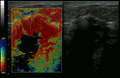

يشير فحص سرطان الثدي إلى اختبار النساء اللائي يتمتعن بصحة جيدة لسرطان الثدي في محاولة لتحقيق تشخيص مبكر على افتراض أن الاكتشاف المبكر سيحسن النتائج. تم استخدام عدد من اختبارات الفحص بما في ذلك الفحص السريري والذاتي فحوصات الثدي وتصوير الثدي والفحص الجيني والموجات فوق الصوتية والتصوير بالرنين المغناطيسي.

ينص تعاون كوكرين (2013) على أن أفضل دليل جودة لا يوضح انخفاضًا في سرطان محدد، ولا انخفاض في جميع أسباب الوفيات الناتجة عن فحص التصوير الشعاعي للثدي.[9] عند إضافة تجارب أقل صرامة إلى التحليل، يحدث انخفاض في معدل الوفيات بسبب سرطان الثدي بنسبة 0.05% (انخفاض 1 كل 2000 حالة وفاة بسبب سرطان الثدي على مدى 10 سنوات أو انخفاض نسبي بنسبة 15% للوفيات بسبب سرطان الثدي).[9] يؤدي الفحص على مدى 10 سنوات إلى زيادة بنسبة 30% في معدلات الإفراط في التشخيص والعلاج الزائد (3 إلى 14 لكل 1000) وأكثر من نصفهم سيحصلون على اختبار واحد إيجابي كاذب على الأقل.[9][118] وقد أدى ذلك إلى الرأي القائل بأنه ليس من الواضح ما إذا كان فحص التصوير الإشعاعي للثدي يفيد أم يضر أكثر.[9] بحسب كوكرين أنه بسبب التحسينات الأخيرة في علاج سرطان الثدي، ومخاطر الإيجابيات الكاذبة من فحص سرطان الثدي التي تؤدي إلى علاج غير ضروري، "لذلك لم يعد من المفيد الحضور لفحص سرطان الثدي" في أي عمر.[119] ليس معروفًا ما إذا كان التصوير بالرنين المغناطيسي كطريقة فحص له أضرار أو فوائد أكبر مقارنةً بالتصوير الإشعاعي للثدي القياسي.[120][121]

تشمل الخيارات الأخرى لأخذ الخزعة الخزعة الأساسية أو vacuum-assisted breast biopsy،[123] وهي الإجراءات التي يتم فيها إزالة جزء من كتلة الثدي؛ أو الخزعة الاستئصالية، حيث يتم إزالة الورم بأكمله. غالبًا ما تكون نتائج الفحص البدني من قبل مقدم الرعاية الصحية والتصوير الشعاعي للثدي والاختبارات الإضافية التي يمكن إجراؤها في ظروف خاصة (مثل التصوير بواسطة الموجات فوق الصوتية أو التصوير بالرنين المغناطيسي) كافية لتبرير الخزعة الاستئصالية كطريقة تشخيصية وعلاجية أولية.[124][بحاجة لمصدر غير رئيسي]